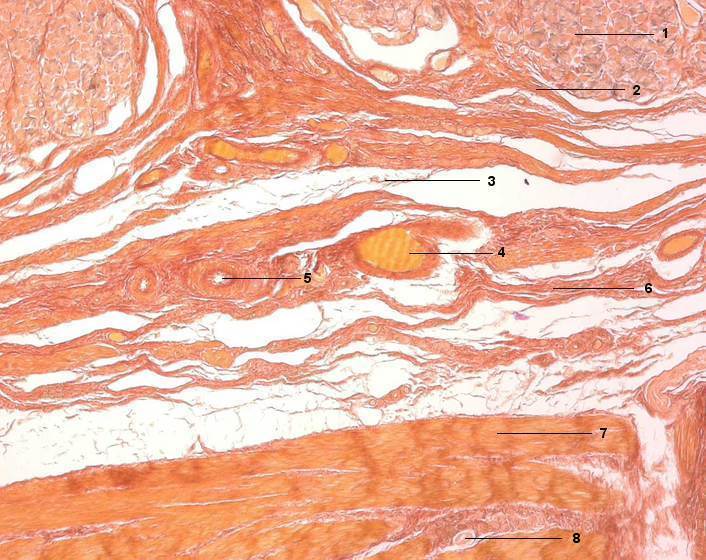

1 Glandulae gastricae (DrĂ¼sengrund)

2 Lamina muscularis mucosae

3 Tela submucosa

4 Vene mit Erythrozyten

5 Arterie

6 Tunica muscularis, Stratum circulare

7 Ganglienzelle des Plexus myentericus